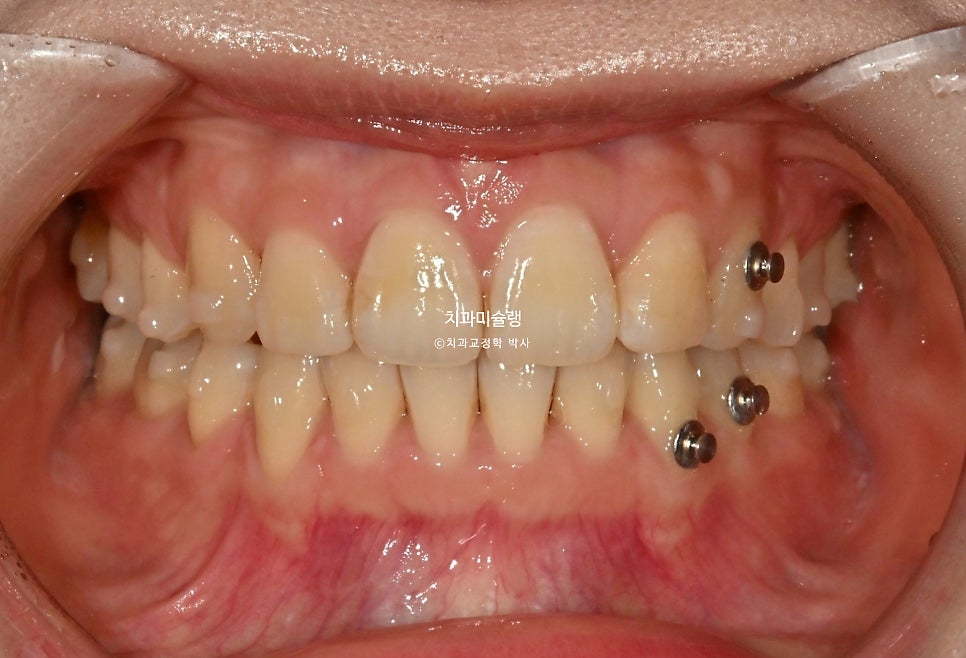

입안을 보면 앞니가 뻗쳐있는 전형적인 돌출 입니다.

위아래 둘다 중절치가 특히 돌출되어 있습니다.

어금니 교합은 물샐틈 없는 1급 교합관계를 보입니다.

이제 전후사진 비교 보겠습니다.

2022.12-2026.02

발치공간은 깔끔히 마무리 되었습니다.